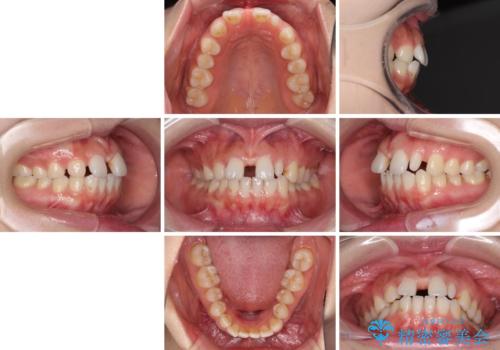

欠損歯と矮小歯 矯正治療と前歯のセラミック治療

- 前歯の隙間を気にして来院された患者様です。

診察の結果、前歯が1本欠損しており、さらに矮小歯(通常よりも小さい歯)が1本存在していました。

欠損による前歯のスペースが大きかったため、事前にワイヤー矯正で前歯の位置を大きく動かし、その後は上下をインビザラインで整えることとしました。

矯正治療後には欠損部はオールセラミックブリッジに、矮小歯はオールセラミッククラウンにて補綴することとしました。

前歯のスペースは、堅い線維の通った歯肉があり、幅も大きかったことから、歯肉切除を行った上でワイヤー矯正により移動を行いました。また、上唇小帯も歯間部付近まで付着していたため、合わせて切除しました。

ワイヤー矯正により、インビザラインよりも早く、歯軸の向きもコントロールしながら移動させることができました。